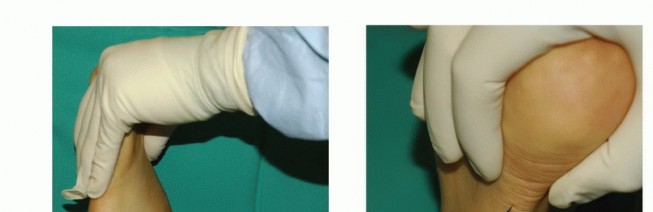

DEFINITION Patellofemoral pain is a common symptom in active adolescents and adults. The diagnosis of patello…